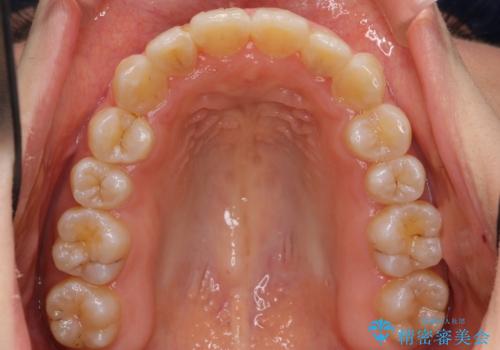

上下の前歯のがたつき 歯を抜かずに矯正

- 上下の前歯のがたつきを主訴に来院。

歯を抜かずに前歯を揃えています。

奥歯を後ろに下げたりなどはしていません。

奥歯を外に広げ、前歯中心に歯を少し削っていますが、健康には問題ない範囲で行なっています。